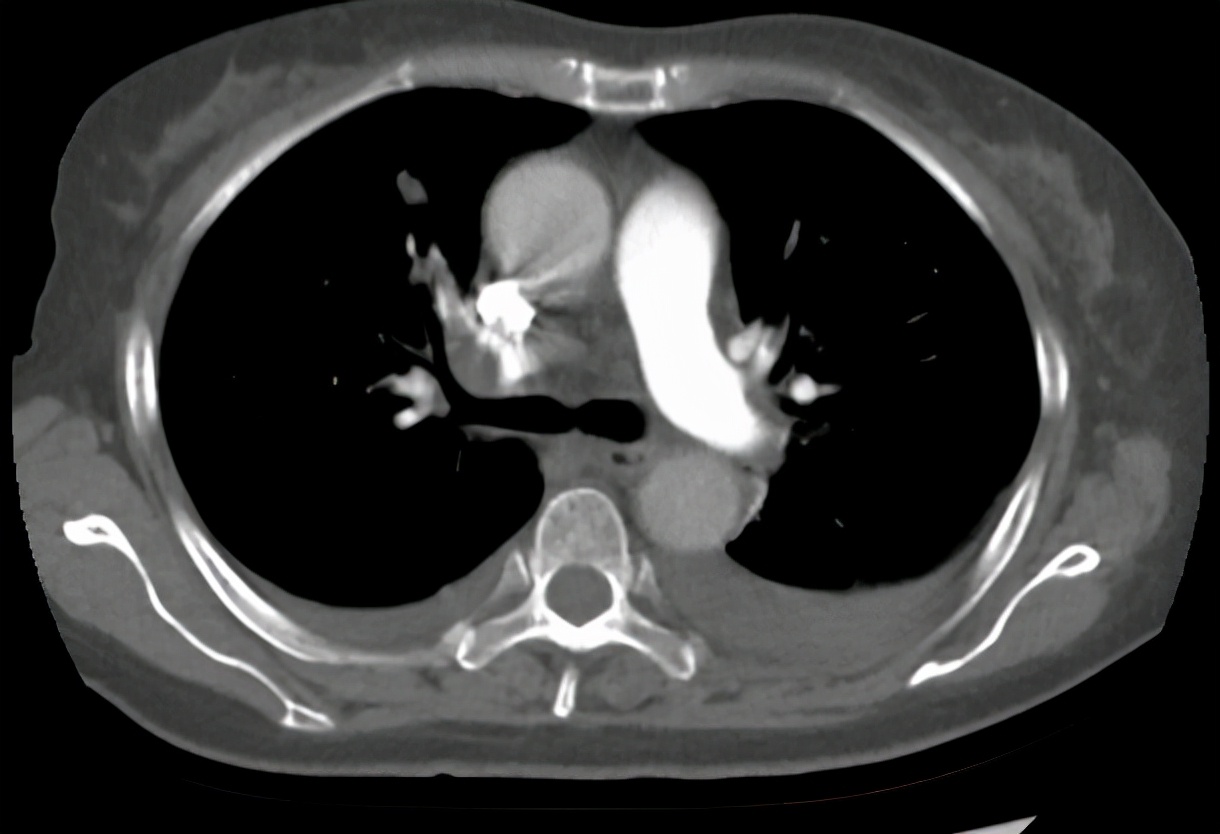

放疗结束后3个月,患者出现胸闷气促,氧饱和度下降,至我科再次就诊,2020-12-23肺动脉CTA:双肺肺动脉多发栓塞。双肺炎症考虑;附见:双侧胸腔积液。考虑患者疾病进展,出现胸腔积液,肺栓塞严重威胁生命,予吸氧、抗凝、化痰、抗感染、营养支持治疗。期间腹胀明显,腹围较前也增大了,肝功能及胆红素进一步升高,考虑有腹水及胆道梗阻可能, 2021-1-6 全腹部CT:胰腺恶性肿瘤化疗后改变,肝脏第二肝门区占位,网膜多发结节灶,考虑转移瘤,建议随诊增强复查。低位性胆道梗阻伴肝内、外胆管明显扩张,胆囊内胆汁淤积。大量腹盆腔积液。予腹腔穿刺引流、护肝、降胆红素治疗,效果不佳,患者精神越来越差,患者想要回家见亲戚朋友最后一面,选择自动出院。

2020-12-23肺动脉CTA